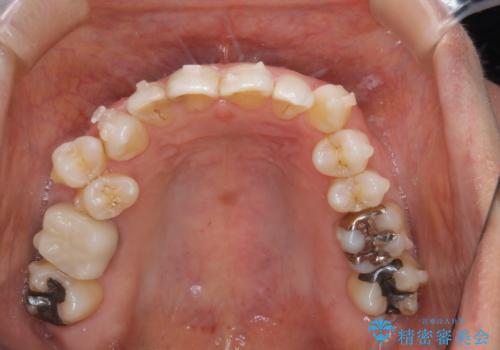

- 右上の小臼歯が二本とも90度捻じれてしまっており、奥歯の噛み合わせに問題が生じていました。

歯を抜いてワイヤー治療を行うという選択肢もありましたが、

奥歯の被せ物の形を適切にすることで非抜歯でも治療が可能であると判断し、

非抜歯、インビザラインでによるマウスピース矯正治療を行うことにいたしました。

今回は右上の奥歯に入っていた銀歯の形が悪く、そのせいで歯を並べるスペースが足りない状態でした。

右上の歯の被せ物を作りなおし、適切な歯の大きさに代えてあげることによってスペースを作りました。

また、それだけではスペースが足りない為右上の奥歯は遠心移動を行っています。